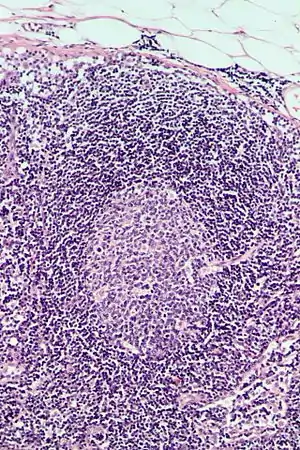

Follicular hyperplasia

Follicular hyperplasia (FH) is a type of lymphoid hyperplasia and is classified as a lymphadenopathy, which means a disease of the lymph nodes. It is caused by a stimulation of the B cell compartment and by abnormal cell growth of secondary follicles. This typically occurs in the cortex without disrupting the lymph node capsule.[1] The follicles are pathologically polymorphous, are often contrasting and varying in size and shape.[2] Follicular hyperplasia is distinguished from follicular lymphoma in its polyclonality and lack of bcl-2 protein expression, whereas follicular lymphoma is monoclonal, and expresses bcl-2.[3]

Follicular hyperplasia can be distinguished among other diseases by observing the density of a lymph follicle on low magnification. Lymph nodes with reactive follicles contain extensions outside its capsule, follicles present throughout the entire node, obvious centroblasts and the absence or diminishing mantle zones. Immunohistochemistry can help distinguish a difference between a patient with follicular lymphoma to follicular hyperplasia.[1] Reactive follicular hyperplasia does not express BCL2 proteins in B cell germinal centers and are absent light chain reaction in immunostaining and flow cytometry as well as absent IG rearrangements.[1]

BCL2 protein expression is usually absent in follicular hyperplasia but prominent in follicular lymphomas. A comparison with other stains that include germinal center markers such as BCL-6 or CD10 is useful to compare when determining a proper diagnosis.[1] CD10 positive cells are metalloproteinase which activate or deactivate peptides through proteolytic cleavage.[9]